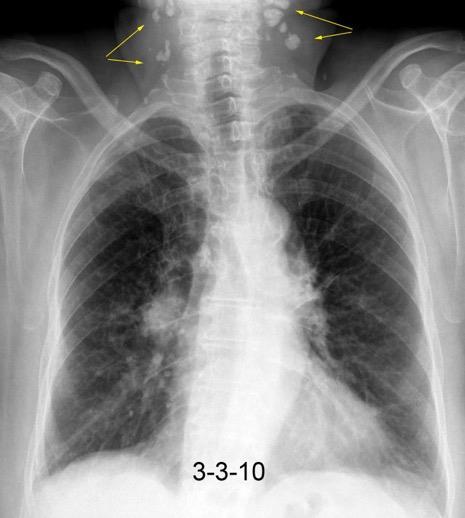

Pliegue axilar Normal

Rehúsa cirugía

2011. Acude por masa axilar

Linfoma NH de cél. B. Invasión Transtorácica.

Afectación axilar